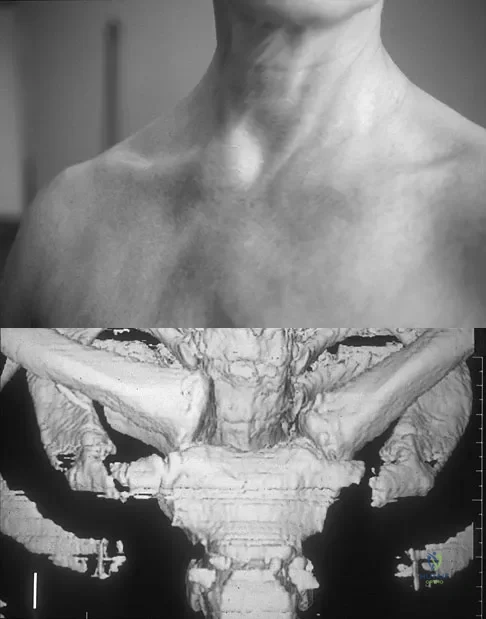

Question 97High Yield

Figure 11a shows the clinical photograph of a 46-year old woman who reports a 3-week history of pain and a "lump" at the base of her neck. She is otherwise in good health and denies any trauma. A 3-D reconstruction CT is shown in Figure 11b. What is the most likely diagnosis?

Explanation